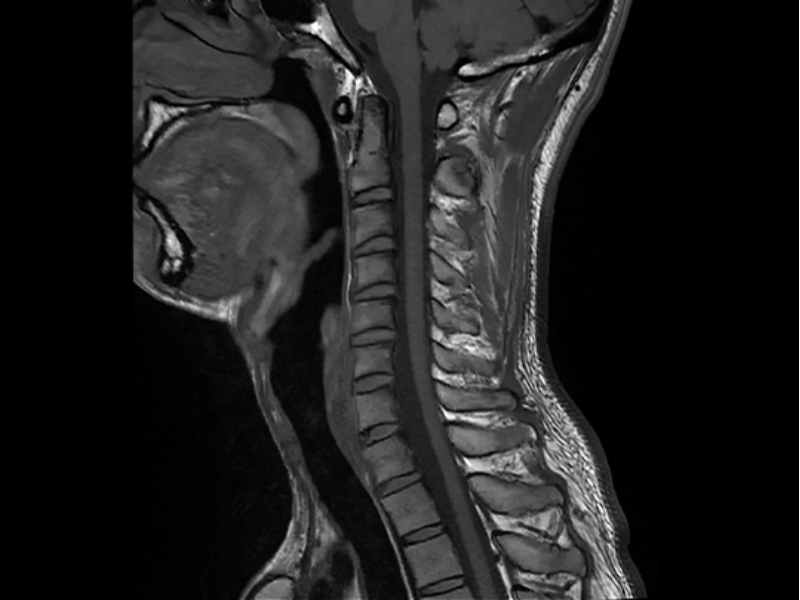

T1W FSE C-Spine